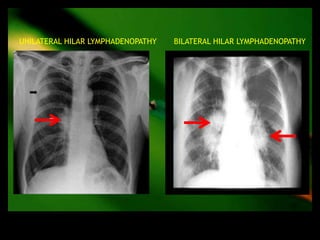

•   Lymphoma

•   Bronchogenic ca

Hilar(u/l)   •

•

TB

sarcoidosis

•   Sarcoidosis

•   Fungal(histoplasmosis,coccidiomycosis)

Hilar(b/l)   •

Lymphoma

Bronchogenic ca

•   TB

UNILATERAL HILAR LYMPHADENOPATHY   BILATERAL HILAR LYMPHADENOPATHY